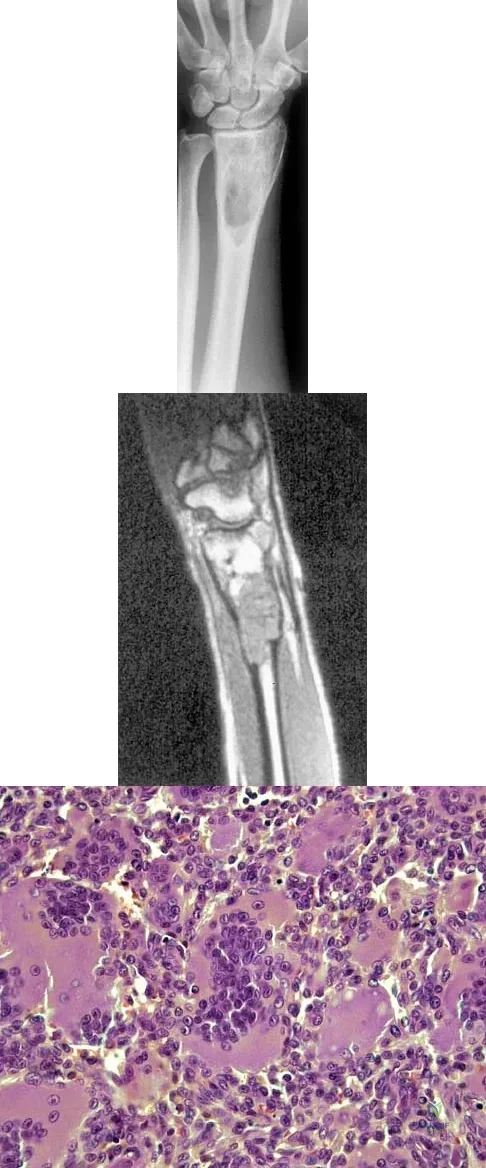

Question 55

Figures 27a through 27c show the AP radiograph, MRI scan, and biopsy specimen of an otherwise healthy man who has a painful wrist. Serum chemistry studies are normal. What is the most likely diagnosis?

Explanation